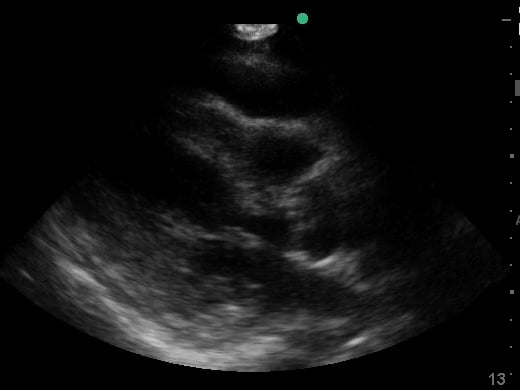

Pericardial effusion in cardiac ultrasound refers to an abnormal accumulation of fluid within the pericardial sac, the double-layered membrane surrounding the heart. This condition can impede the heart’s ability to fill and pump blood effectively, potentially leading to cardiac tamponade, a life-threatening emergency. Early detection through echocardiography is crucial for timely medical intervention and improved patient outcomes.

Utilizing medical ultrasound, healthcare professionals can accurately identify and quantify pericardial effusions, assessing their size, location, and hemodynamic impact. Ultrasound imaging provides real-time visualization of the fluid build-up, enabling precise diagnosis and guiding potential therapeutic procedures such as pericardiocentesis. This non-invasive technique is indispensable for managing cardiac health and preventing severe complications.